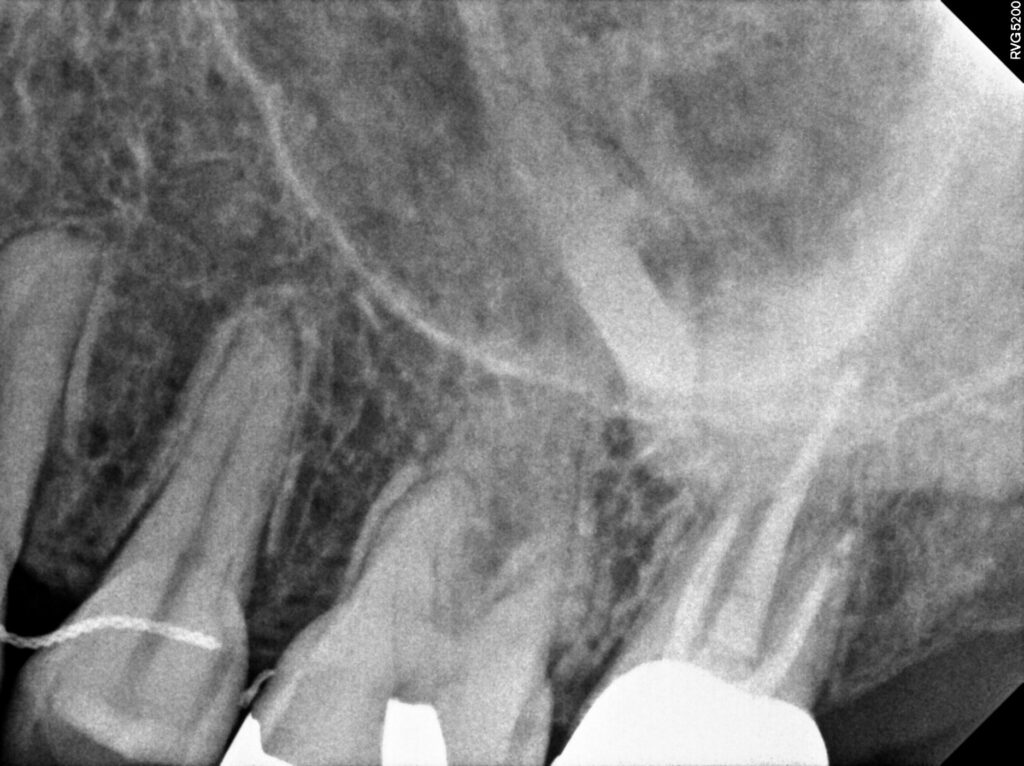

이어서 2024년에 왼쪽 위 가장 안쪽 어금니에

통증이 있어 타 치과에서 재신경치료가 어렵다고 하여

발치권고를 받으셨으나 광화문치과에서

재신경치료를 진행하셨는데요.

잘 맞지 않았던 기존 보철물을 제거하고

내부의 단단한 재료인 코어부터 제거하여

다시 재충전후 보철을 진행하여 현재까지

통증 없이 현재까지 잘 유지하고 계십니다.